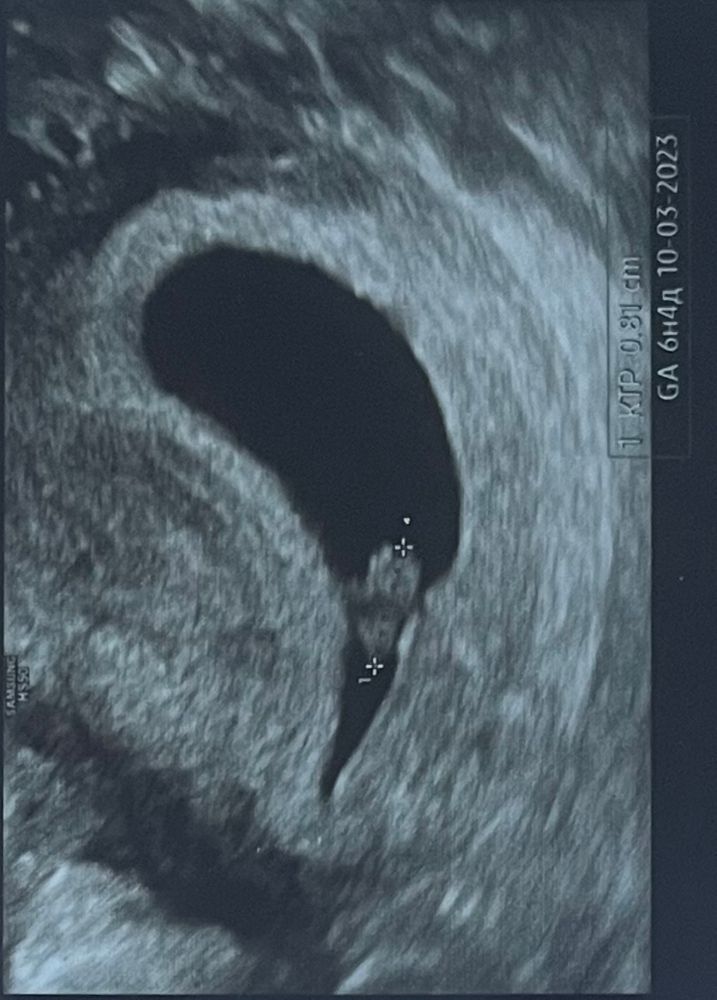

6 недель, отзеркалила.

Так было в оригинале по животу

Подскажите, кто наша креветочка?